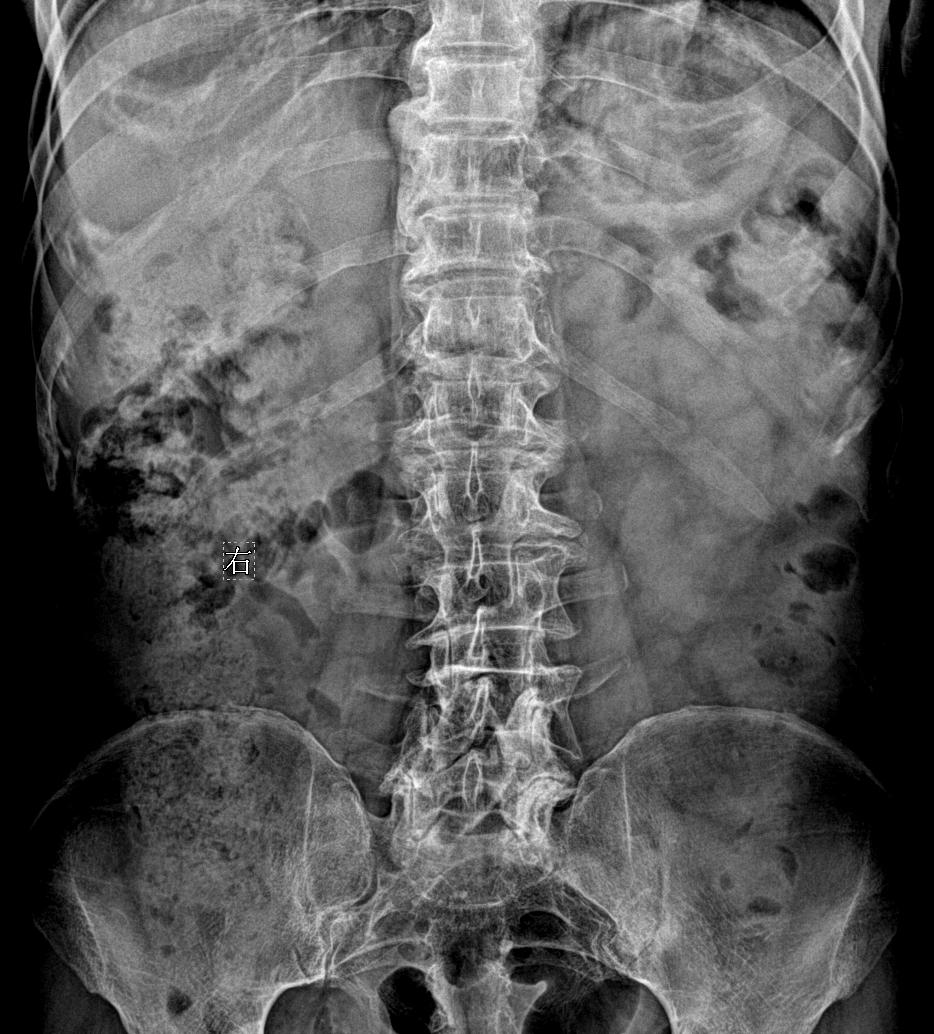

男,79y,腰疼就诊

腰椎疼痛,下肢麻木酸疼

腰椎疼痛,滑脱几度?